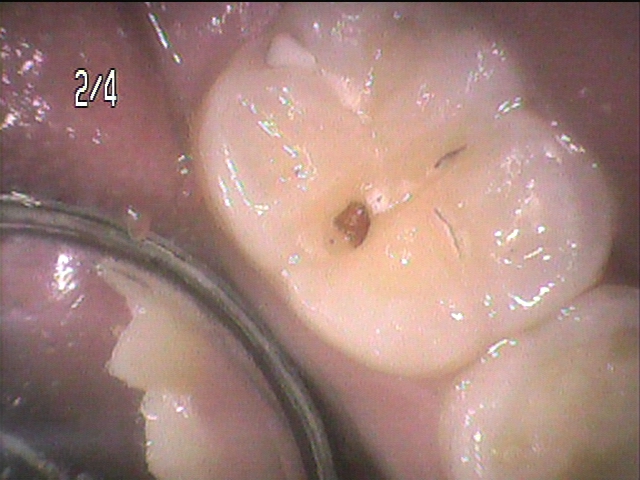

虫歯の治療をしてみると見た目以上に深い虫歯です。

典型的な急性虫歯の症状です。

虫歯をMIバー(健全な歯質をなるべく削らないように設計された径の小さなバー)で取り除きます。